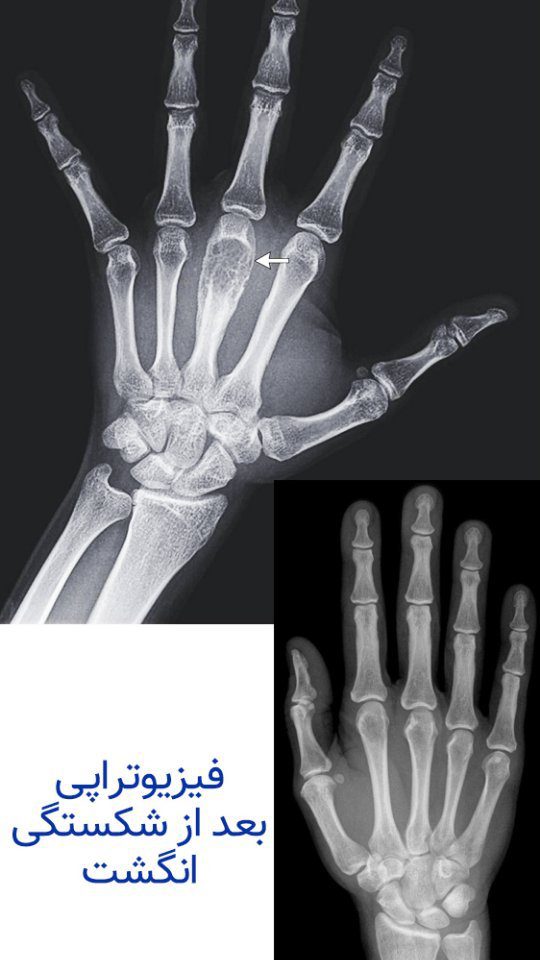

فیزیوتراپی بعد از شکستگی انگشت دست

درمان محدودیت حرکتی و درد و التهاب ناشی از حراجی شکستگی استخوان های متاکارپ دست با استفاده از مدالیتی های مختلف فیزیوتراپی و همچنین تکنیک های درمان دستی و تمرین درمانی

بعد از هر شکستگی به علت روند جراحی و جوش خوردن بافت استخوانی برای اندام توسط آتل و یا گچ بیحرکتی تجویز میشود و این بی حرکتی باعث محدودیت و خشکی مفاصل و عضلات اطراف آن میشود نقش فیزیوتراپی انگشت دست در درمان محدودیت حرکتی و درد و التهاب ناشی از جراحی بسیار کمک کننده و تاثیر گذار است .